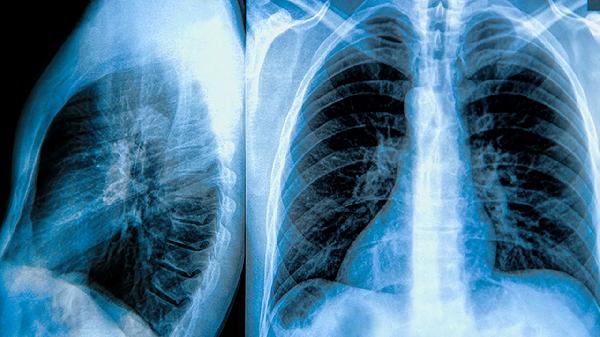

肺大泡患者可通过中药调理缓解症状,常用有效药材包括黄芪、浙贝母、丹参,分别针对气虚、痰瘀、血瘀等核心病机。